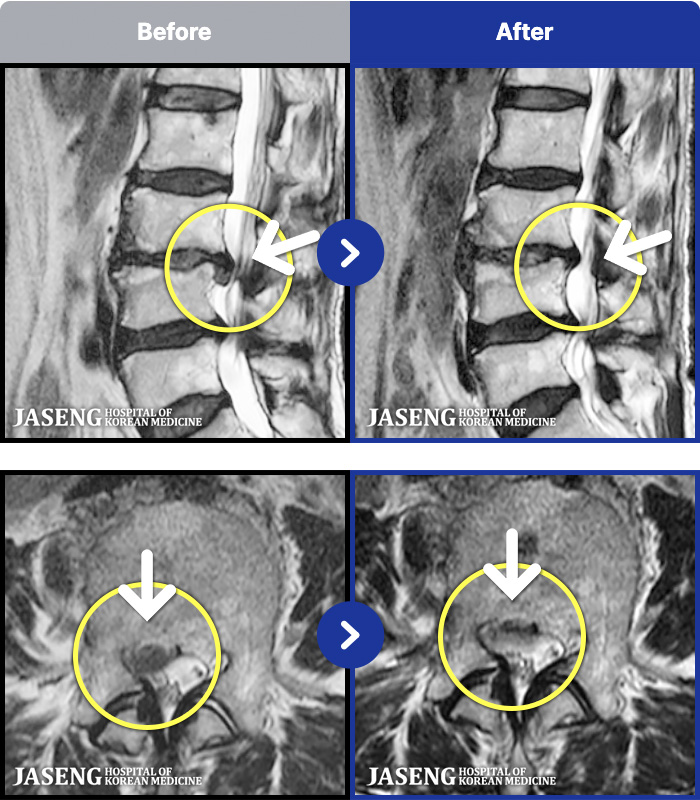

MRI ġ

1,299 MRI ũ ʸ Ȯϼ.